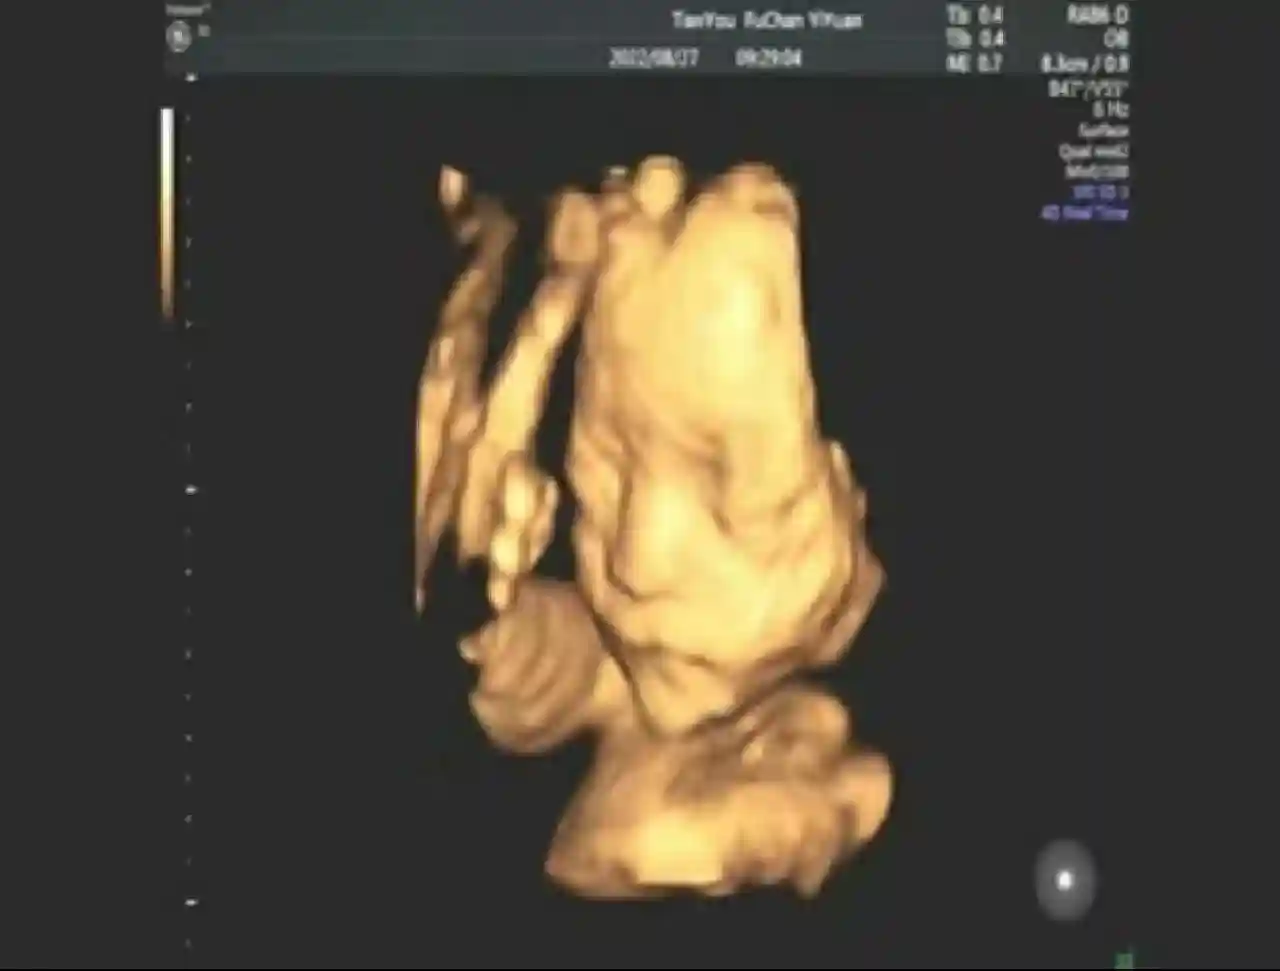

最终还是选择了共泡泡试管,可能中间有过太过的煎熬与纠结,好在结果很好37岁高龄如愿抱到了小🤴,

希望更多的高龄姐妹接好孕,不放弃